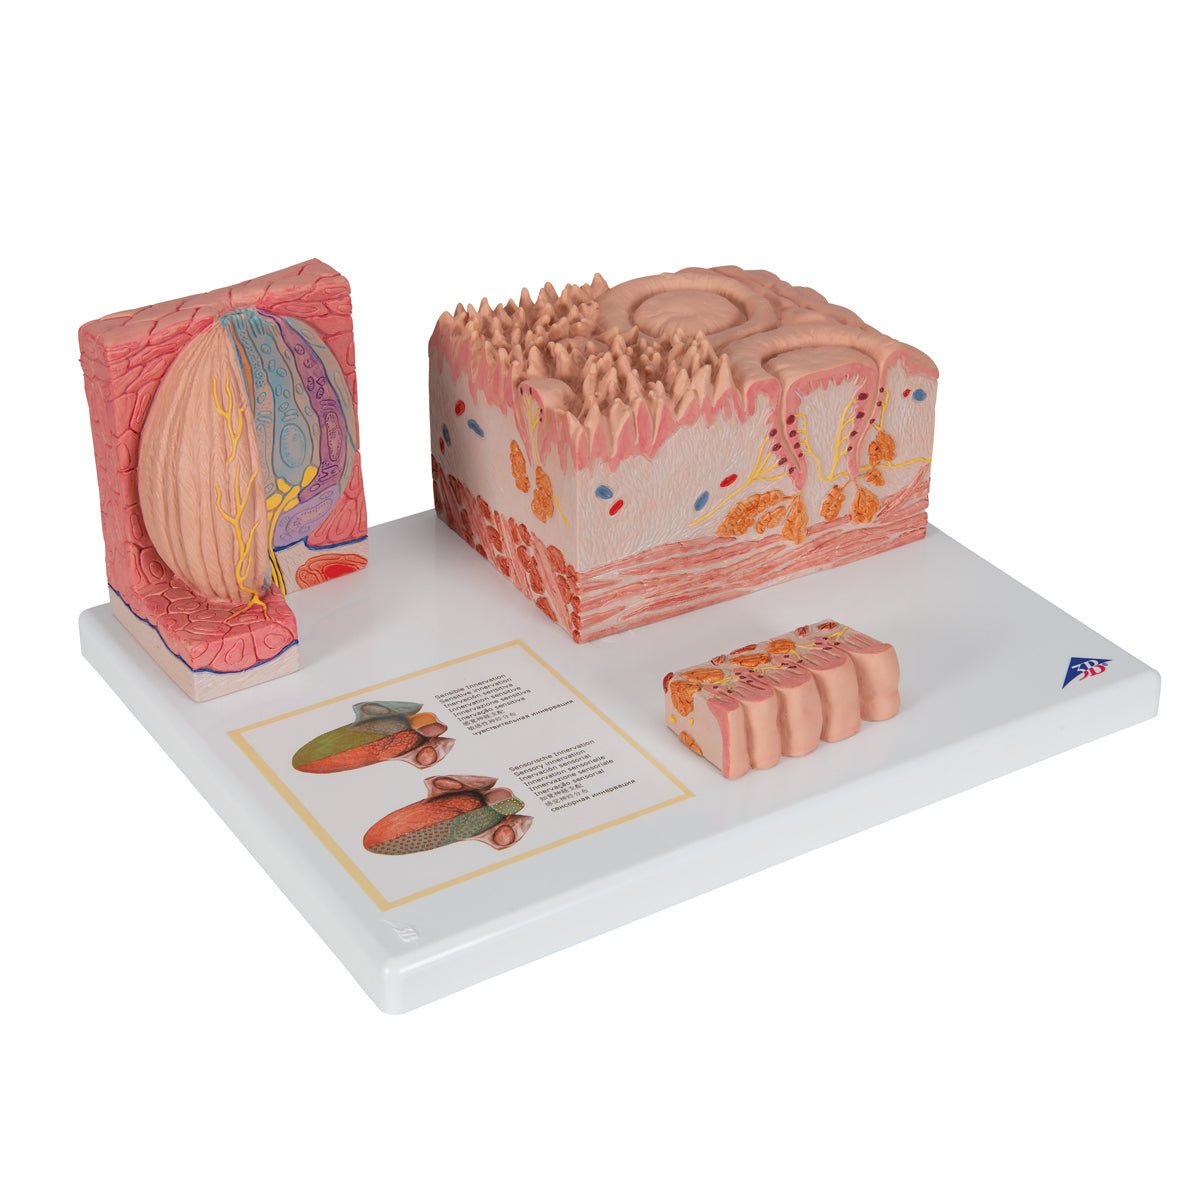

Salg af anatomiske modeller er det bærende element i eAnatomi, selvom vi også bruger mange ressourcer på at udvikle vores egne anatomiske materialer som fx plakater. Anatomiske modeller anvendes til forskellige formål og kan både vise afgrænset væv, organer samt organsystemer. Søger du en simpel model af knoglevæv eller måske en avanceret torso-model baseret på MRI teknologi, kan du finde det hele på eanatomi.com.